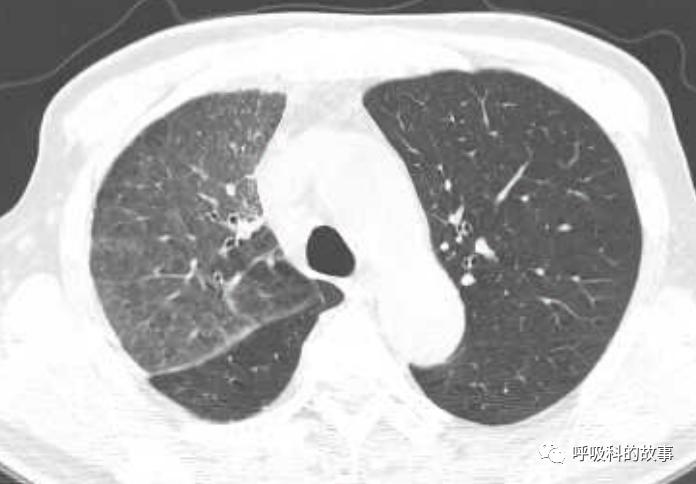

所以如果我们能对这些特征有所了解,那么其实诊断肺马尔尼菲蓝状菌感染并不是什么难事。后来我们又遇到一个肺部结节的患者(如下图):

大家可以发现这个小结节外周有晕征,内部有一小空洞,更重要的是纵隔淋巴结肿大,因此我们马上考虑到肺马尔尼菲蓝状菌感染,进行气管镜检查,做纵隔淋巴结穿刺培养出马尔尼菲蓝状菌。